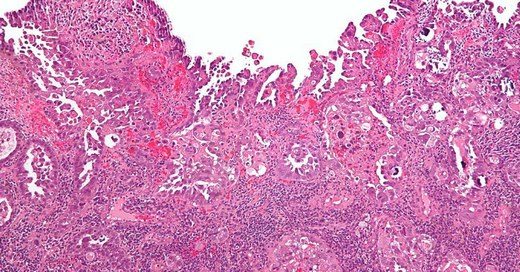

if you say we are confused doctor what is cin what is lsil come to this section genital sigil hpv human papilloma virus